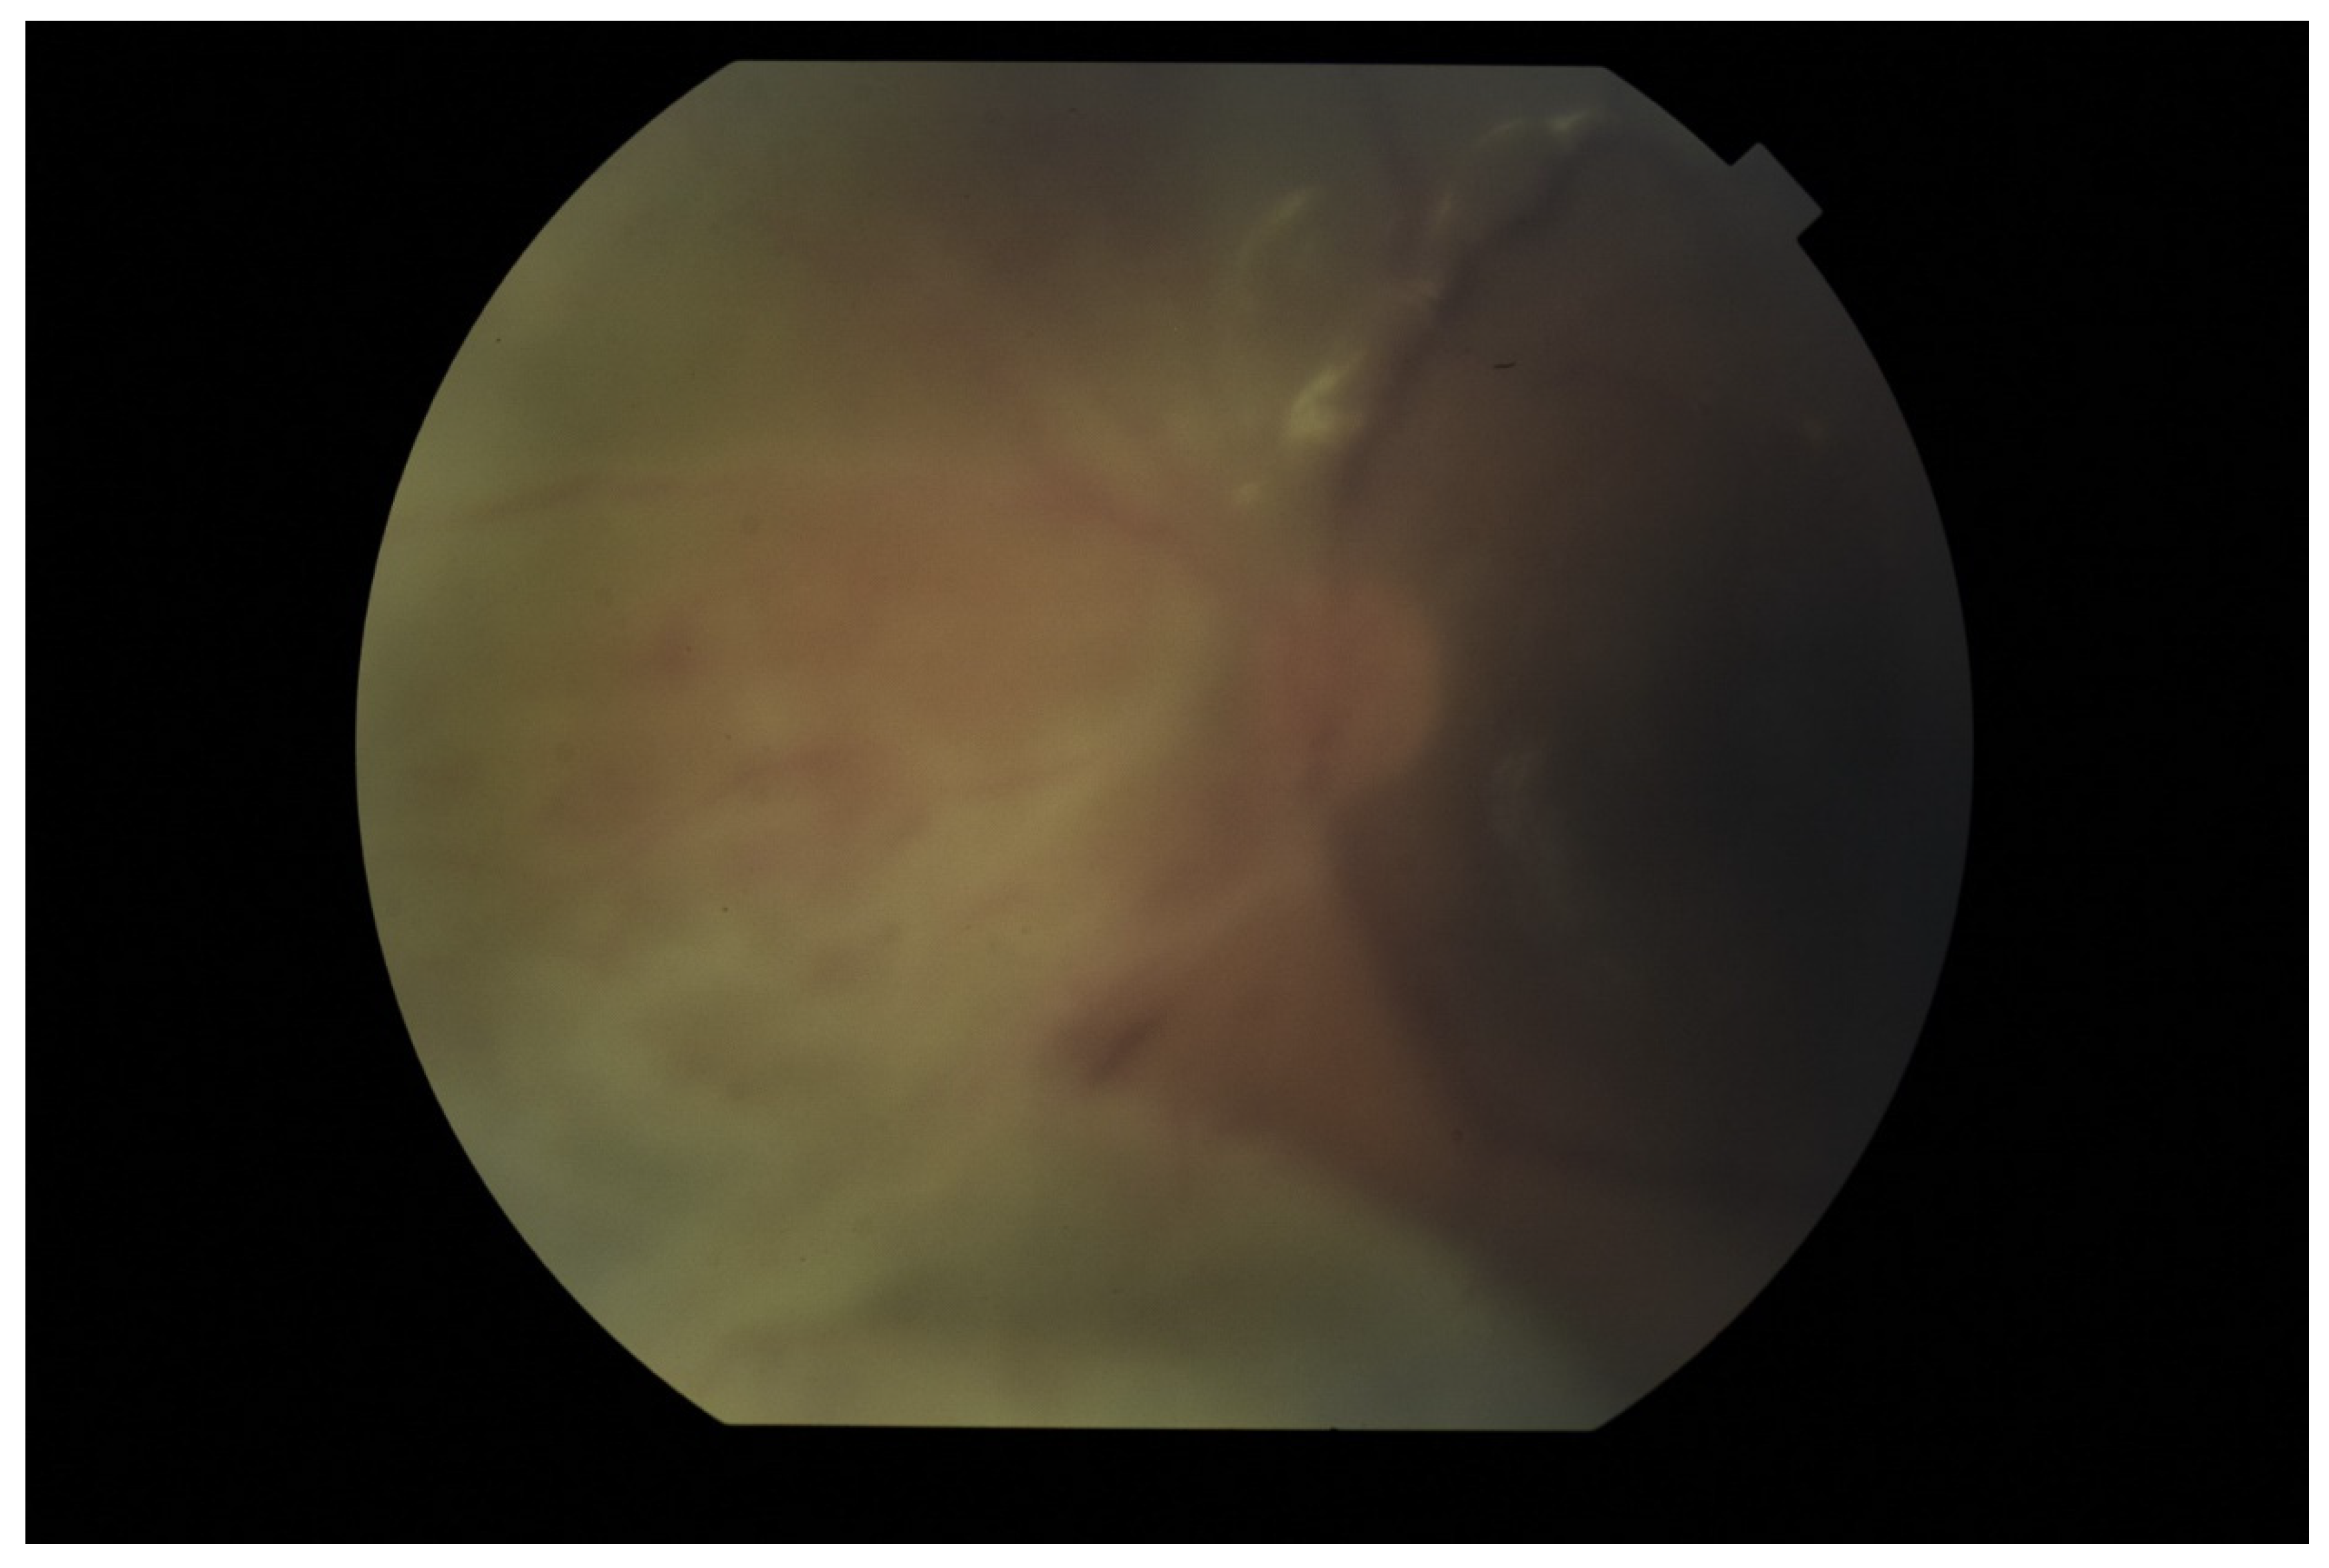

The tendency to abscess formation in the course of Klebsiella infection is also reflected in eye. One of the rare but characteristic feature of EE in the course of Klebsiella infection is the formation of subretinal abscesses [26]. They take the form of retinal elevation and paleness (Figure 1 and Figure 2). With properly selected antibiotic therapy, even large abscesses may be absorbed. If the patient is undergoing vitrectomy, intraoperative drainage may be considered [27].

Figure 1.

Fundus pictures of subretinal abscess, taken on the second day after vitrectomy. Partially drained abscess is visible, located nasally from the optic disc. Poor image quality is caused by the presence of inflammatory cells in the anterior chamber.